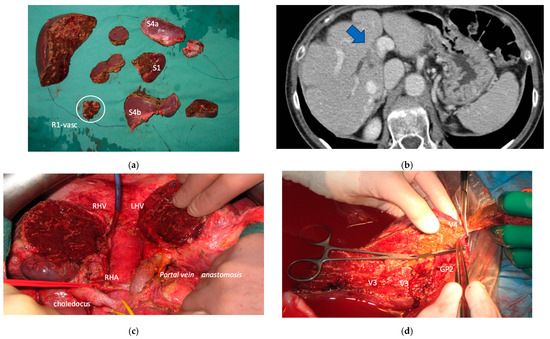

Figure 1. PS-TSH with SS-PVE. The parenchyma-sparing TWO-STAGE major hepatectomy with super-selective PVE is proposed when preservation of a second-order GP is planned and FLR volume is less than 40%. (a) Whole liver. (b) First stage: vessel-guided mesohepatectomy of S1/S4 en-bloc with MHV for liver partition (MLP). (c) Super-selective PVE of the anterior portal branch for S5/S8 and of the portal branch for S7, preserving the portal branch for S6. (d) Second stage: vessel-guided resection of embolized liver. At the end of PS-TSH there are two livers: one on the right constituted by S6, and one on the left constituted by S2/S3. Abbreviations: PS: parenchyma sparing; TSH: two-stage hepatectomy; SS-PVE: super-selective portal vein embolization; GP: glissonean pedicle; FLR: future liver remnant; MHV: middle hepatic vein; MLP: mesohepatectomy for liver partition; S: segment.

Figure 7. Intraoperative field images of PS-TSH with SS-PVE performed to treat 35 bilateral CRLMs. (a) Hole liver at the first stage after FOLFOXIRI + Bevacizumab 12 cycles, with liver transection lines (yellow dotted lines). (b) At the end of the first stage of TS-PSH with SS-PVE: resection of S1/S4 extended to S2/S8/S5 plus metastasectomy of S2 with tangential resection of LHV, first-order GPs are completely exposed; the primary is resected with a simultaneous right hemicolectomy. (c) At the end of the second stage performed 58 days after the first stage, embolized liver is completely resected and S5 only is preserved, the left liver remains untouched. (d) At the second stage S5 was twisted to avoid kinking of RHV which is completely skeletonized, for this reason GPs 6–7 and GP 8 appear inverted. Abbreviations: PS-TSH: parenchyma-sparing TWO-STAGE hepatectomy; SS-PVE: super-selective portal vein embolization; CRLM: colorectal liver metastases; RHV: right hepatic vein; LHV: left hepatic vein; V4: scissural hepatic vein; S: segment; GP: glissonean pedicle; UP: umbilical portion.

In all 15 cases planned vessel-guided MLP was successfully carried out. For the surgical approach, a J-shaped laparotomy was used in 13 cases and the xipho-pubic incision in two; no thoraco-abdominal incision was needed. In two cases of MLP performed as the first stage of ALPPS, liver partition was obtained with a single transection line: in one case (FLR = S2/S3/S4b) between a part of S4b and S5 since S4a/S1 were resected in previous e-OSH, in the other case (FLR = S4/S2/Spiegel lobe) the single transection line preserved part of S4a/S4b and the Spiegel lobe. In 11 cases liver partition was obtained with a minor mesohepatectomy: in one case with resection of S4a/S1 partially extended to S5 preserving S4b, in two cases with resection of S1/S4 preserving the Spiegel lobe, in one case with resection of segments S5/S8 extended to the caudate processus of S1 preserving the Spiegel lobe and paracaval portion of S1 and in the other seven cases with anatomic resection of S1/S4 (see Figure 4).

Liver partition was obtained with a major mesohepatectomy in two cases with anatomical resection of S1/S4/S8 (en-bloc with biliary tree in one, see Figure 5).